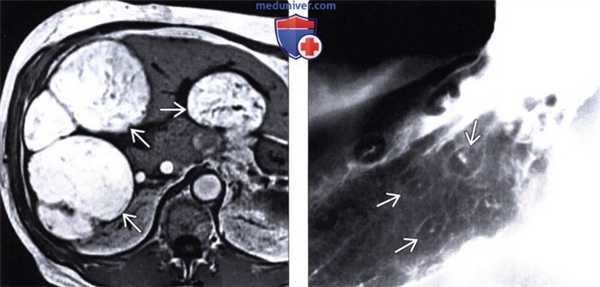

(Слева) На аксиальной МР томограмме (Т1-ВИ) визуализируются множественные метастазы, дающие характерный гипоинтенсивный сигнал на Т1-ВИ, обусловленный высоким содержанием меланина в них. В похожих случаях, метастазы, содержащие жир или кровь, также могут выглядеть гиперинтенсивными на Т1-ВИ.

(Справа) В верхних отделах ЖКТ определяются «классические» поражения в виде «бычьего глаза», представляющие собой мелкие внутристеночные объемные образования с изъязвлением в центре. Лимфома и саркома Капоши также могут проявляться схожими изменениями.

(Слева) При МРТ в аксиальной плоскости на Т1ВИ в пяточной области со стороны подошвы определяются небольшие овоидные поверхностно расположенные узелки, слабогиперинтен-сивные по сравнению с мышцами.

(Справа) У этого же пациента при МРТ в аксиальной плоскости на Т2ВИ в режиме FS данные узелки характеризуются гиперинтенсивным сигналом. Они представляют собой сателлитные метастазы первичной меланомы, которую несколькими годами ранее «прижег» врач. Несмотря на то, что эти образования были видны и при осмотре, для обнаружения в данной области всех возможных опухолей и планирования их резекции была выполнена МРТ. (Слева) У этого же пациента при МРТ с контрастным усилением в коронарной плоскости на Т1ВИ в режиме FS определяется контрастирование небольших сателлитных метастазов меланомы. Несмотря на то что при ПЭТ/КТ другие образования выявлены не были, уже через год в бедре этой же конечности был обнаружен транзитный метастаз.

(Справа) При ПЭТ в коронарной плоскости визуализируются множественные очаги накопления РФП, соответствующие метастазам меланомы. Такая картина оказалась не ожиданной, поскольку это было первичное исследование у пациента с бессимптомной меланомой предплечья размером 8 мм. (Слева) У этого же пациента при мультипланарной ПЭТ/КТ в мышцах левого бедра определяется метастаз меланомы (SUVмакс = 18,7). Образование характеризуется слабо пониженной плотностью по сравнению с мышцами при нативной КТ.

(Справа) У этою же пациента при КТ с контрастным усилением в костной ткани над вертлужной впадиной слева визуализируется доминантный метастаз. Он характеризуется литической структурой и деструкцией кортикального слоя кости. Также в подкожной клетчатке виден еще один метастаз.